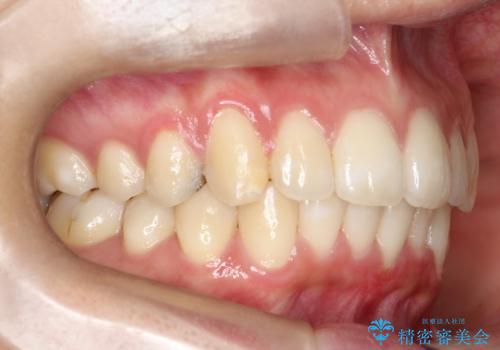

- 前歯のでこぼこが気になると来院されました。

奥歯の噛み合わせは綺麗に噛んでいたため、前歯の叢生(でこぼこ)を、短期間で治療完了するように計画しました。

奥歯の噛み合わせは整っていたため、前歯の並びを美しく修正することに専念できました。マウスピース矯正による治療で短期間で改善しました。